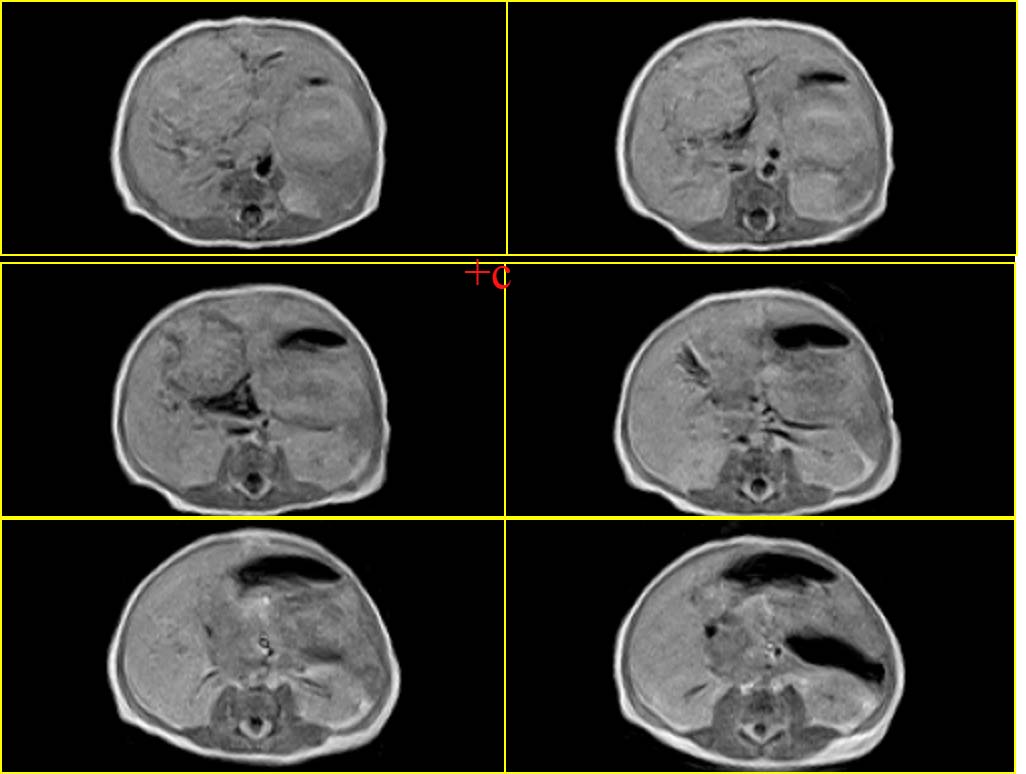

血管内皮瘤,建议补充临床资料,如血常规,尤其血小板情况,有无充血性心衰,主要与肝母鉴别.

考虑肝母